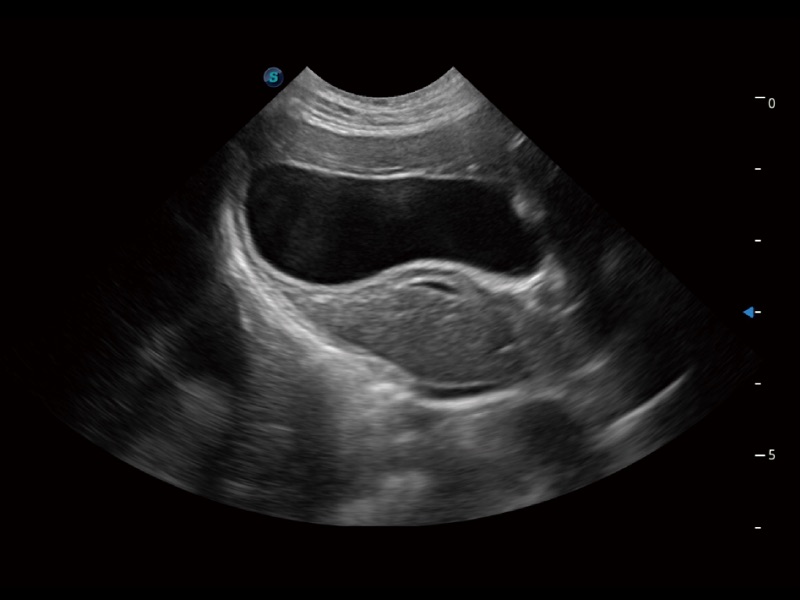

动物是人类最亲密的朋友和最值得信赖的伙伴。16877太阳集团也一直致力于探索动物专用的超声影像解决方案。全新推出的ProPet系列,是16877太阳集团在动物超声影像智能化、专业化、精准化的一次跨越式革新。动物不能用言语来表述自己的不适,通过超声影像,ProPet系列搭建了动物医生与不同物种沟通的“桥梁”,为动物医生注入了“治愈之力”。 ProPet 70将是您值得信赖的超声伙伴。它配备了复合材料线阵探头,帮助动物医生获得卓越精准的临床图像。同时ProPet 70直观便捷的操作体验以及专业的测量工具,可为不同体型和生理结构的动物带来全面临床评估,切实为动物医生提供智能、专业、精准的超声影像解决方案。

ProPet 70 进一步提升了微米成像算法,更加注重对基础原始图像的还原和保留,在有效减少斑点噪声、增强组织边界显示的同时,避免过度优化丟失真实的解剖信息。

ProPet 70专为动物医生设计,对不同的动物体型和生理结构作出了针对性的优化。通过动物影像专用软件,可满足个性化的应用需求,帮助动物医生获得更精确的诊断数据。

ProPet 70 全新的动物超声智能软件和丰富的探头群,为动物医生提供了高清晰度和精细分辨率的图像,无论在宠物、马科、畜牧还是实验室动物等应用中都可以轻松应对,为您的日常工作带来满意的体验。